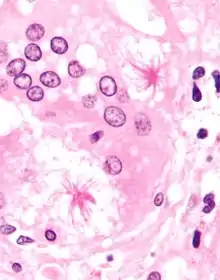

Two asteroid bodies. H&E stain.

An asteroid body is a microscopic finding seen within the giant cells of granulomas in diseases such as sarcoidosis and foreign-body giant cell reactions.[1]

There is controversy about their composition. Traditionally, they were thought to be cytoskeletal elements and to consist primarily of vimentin.[2] However, more recent research suggested that that was incorrect and that they may be composed of lipids arranged into bilayer membranes.[3]

They were also once thought to be related to centrioles,[4] an organelle involved in cell division in eukaryotes.